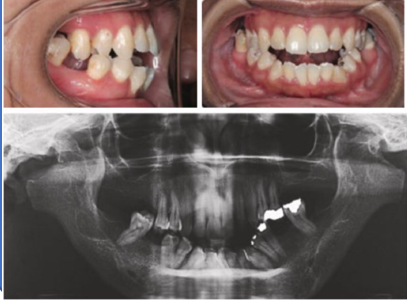

Oral Assessments:

Records show:

1. Anterior open bite

2. Class II malocclusion

3. Maxillary hypoplasia

4. Narrow palate

5. Increased buccal corridors upon smiling